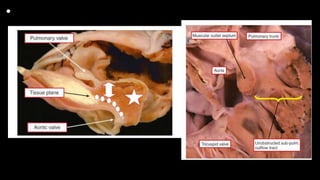

• An autopsied

specimen has

been opened

through the

anterior wall of

the right ventricle

to show the

cardinal features

of tetralogy of

Fallot.

• In this specimen, also

photographed in a

fashion comparable for

the heart shown in

Figure 1, there is

muscular tissue

interposed between the

leaflets of the aortic and

tricuspid valves in the

postero-inferior margin

of the ventricular septal

defect.